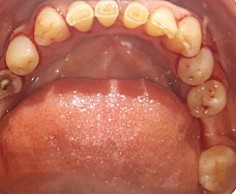

• Modelos de estudio y  fotografías intraorales

Modelos de estudio y fotografías intraorales

Referencia a una réplica exacta de la estructura dental del paciente.